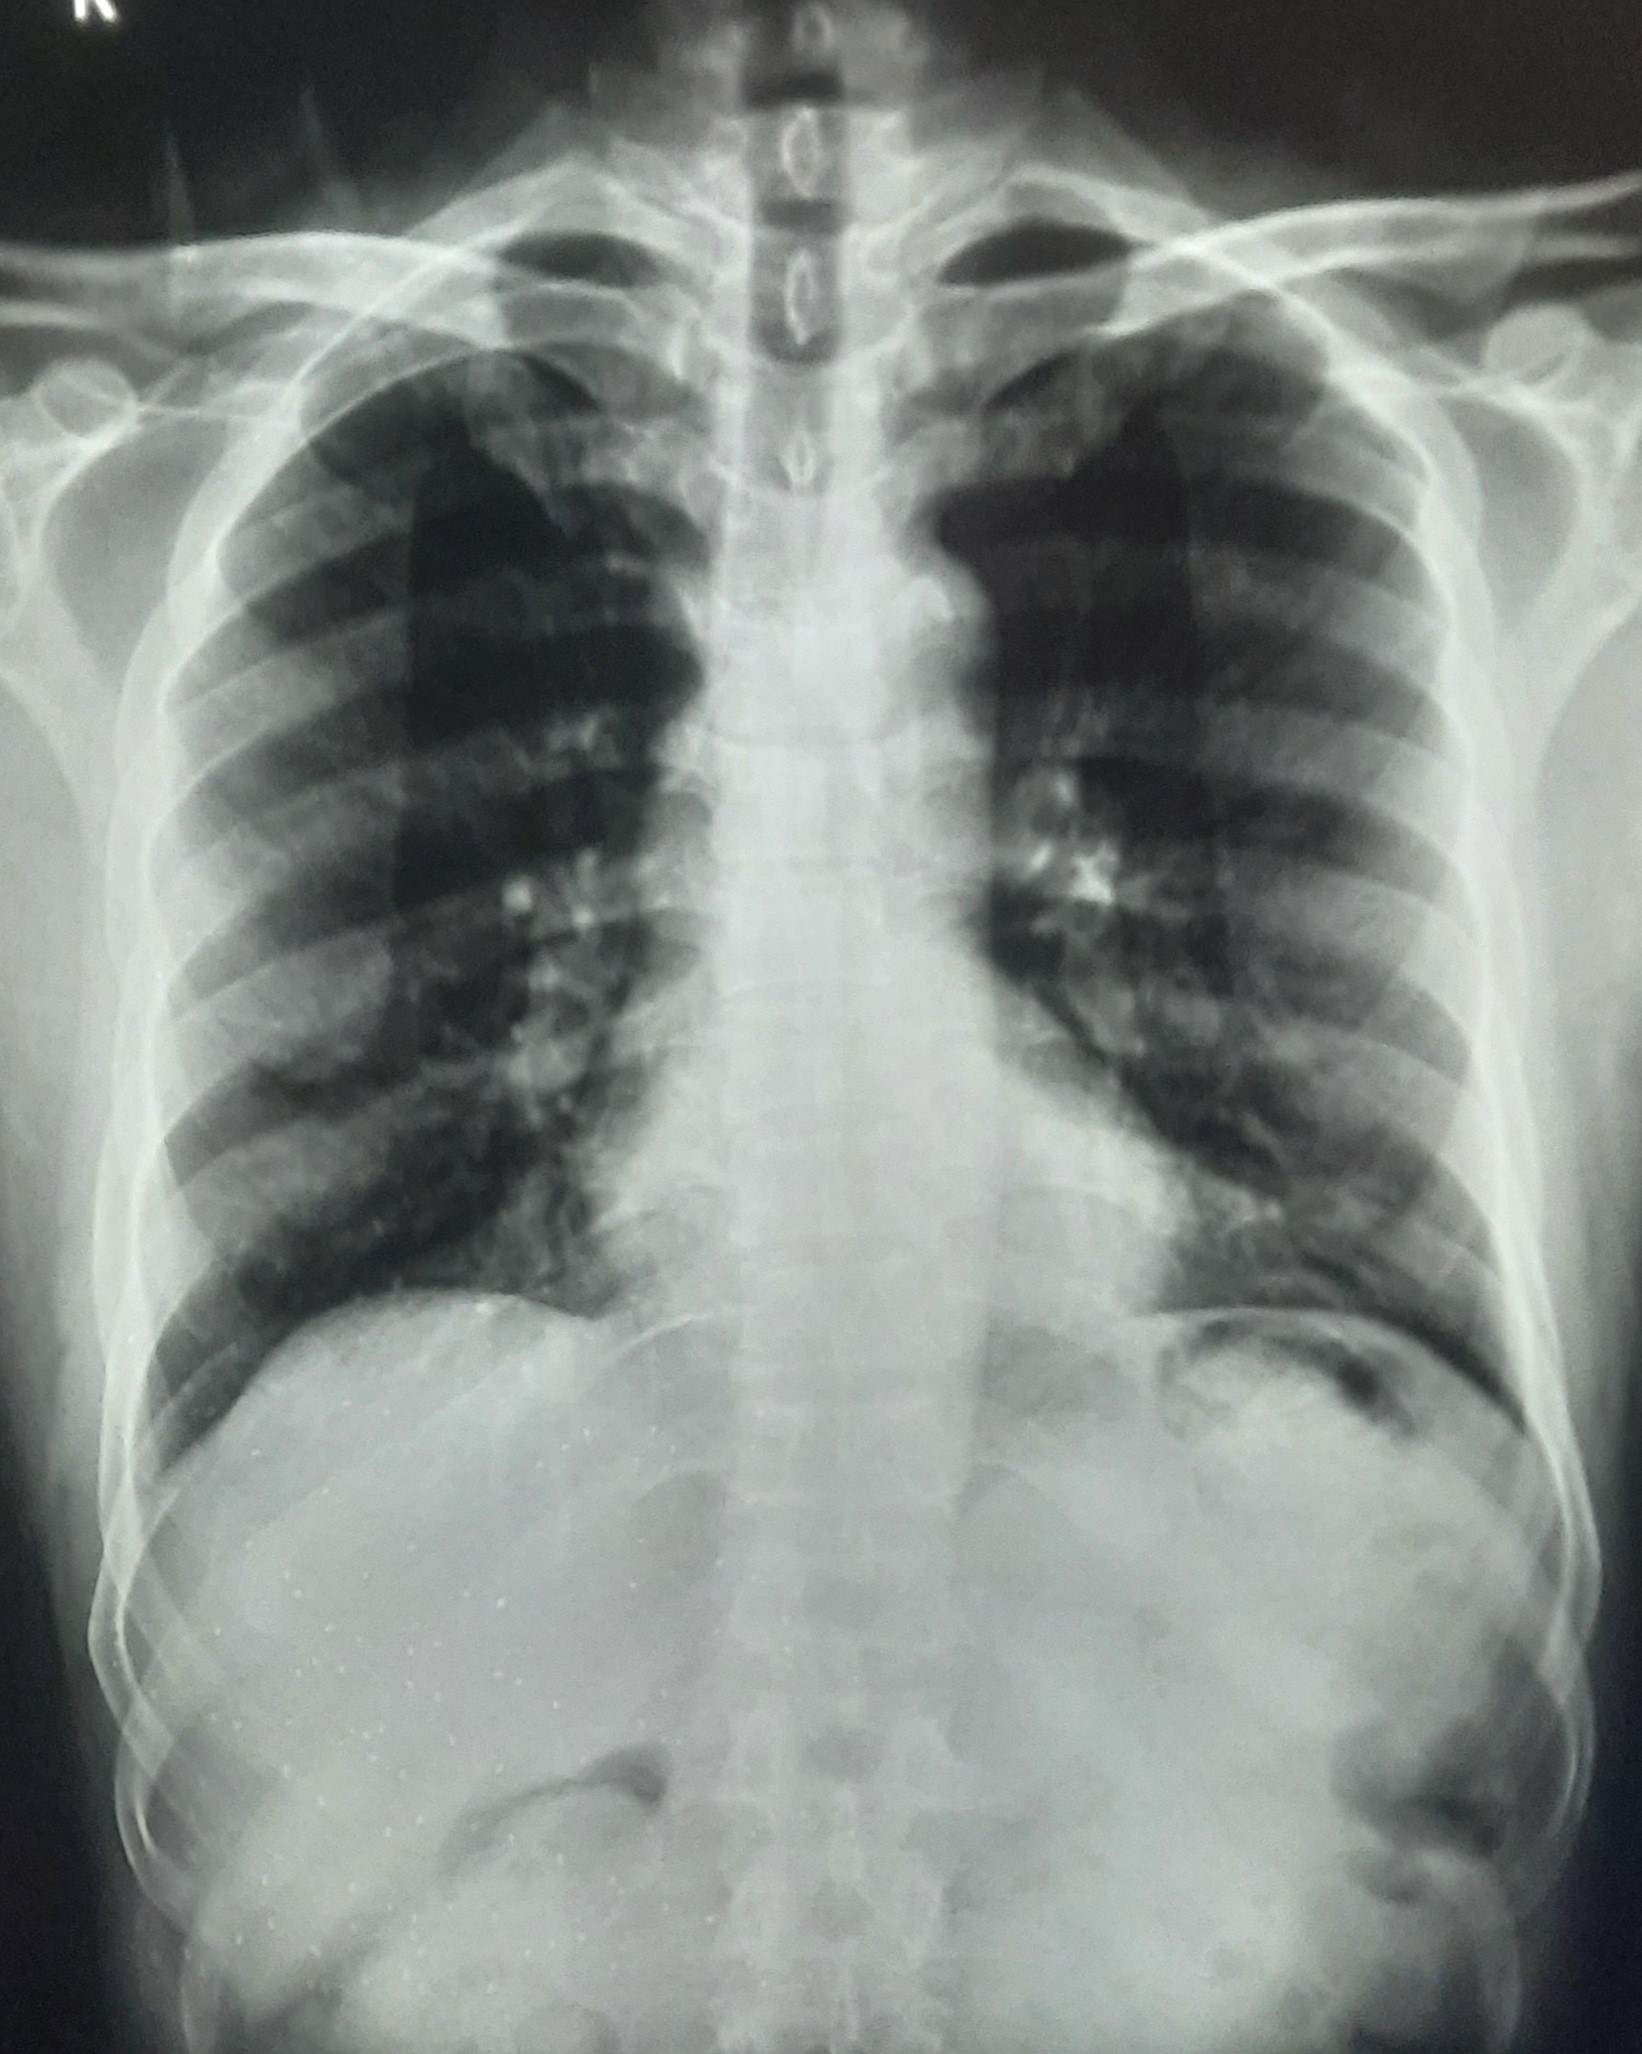

| IGGMC, Nagpur | 29-4198 | IGGMC, Nagpur | Ravindra Purushottam Moundekar | F/C/O Rhinosinusitis 2 Year |

| Chest X-Ray Image |